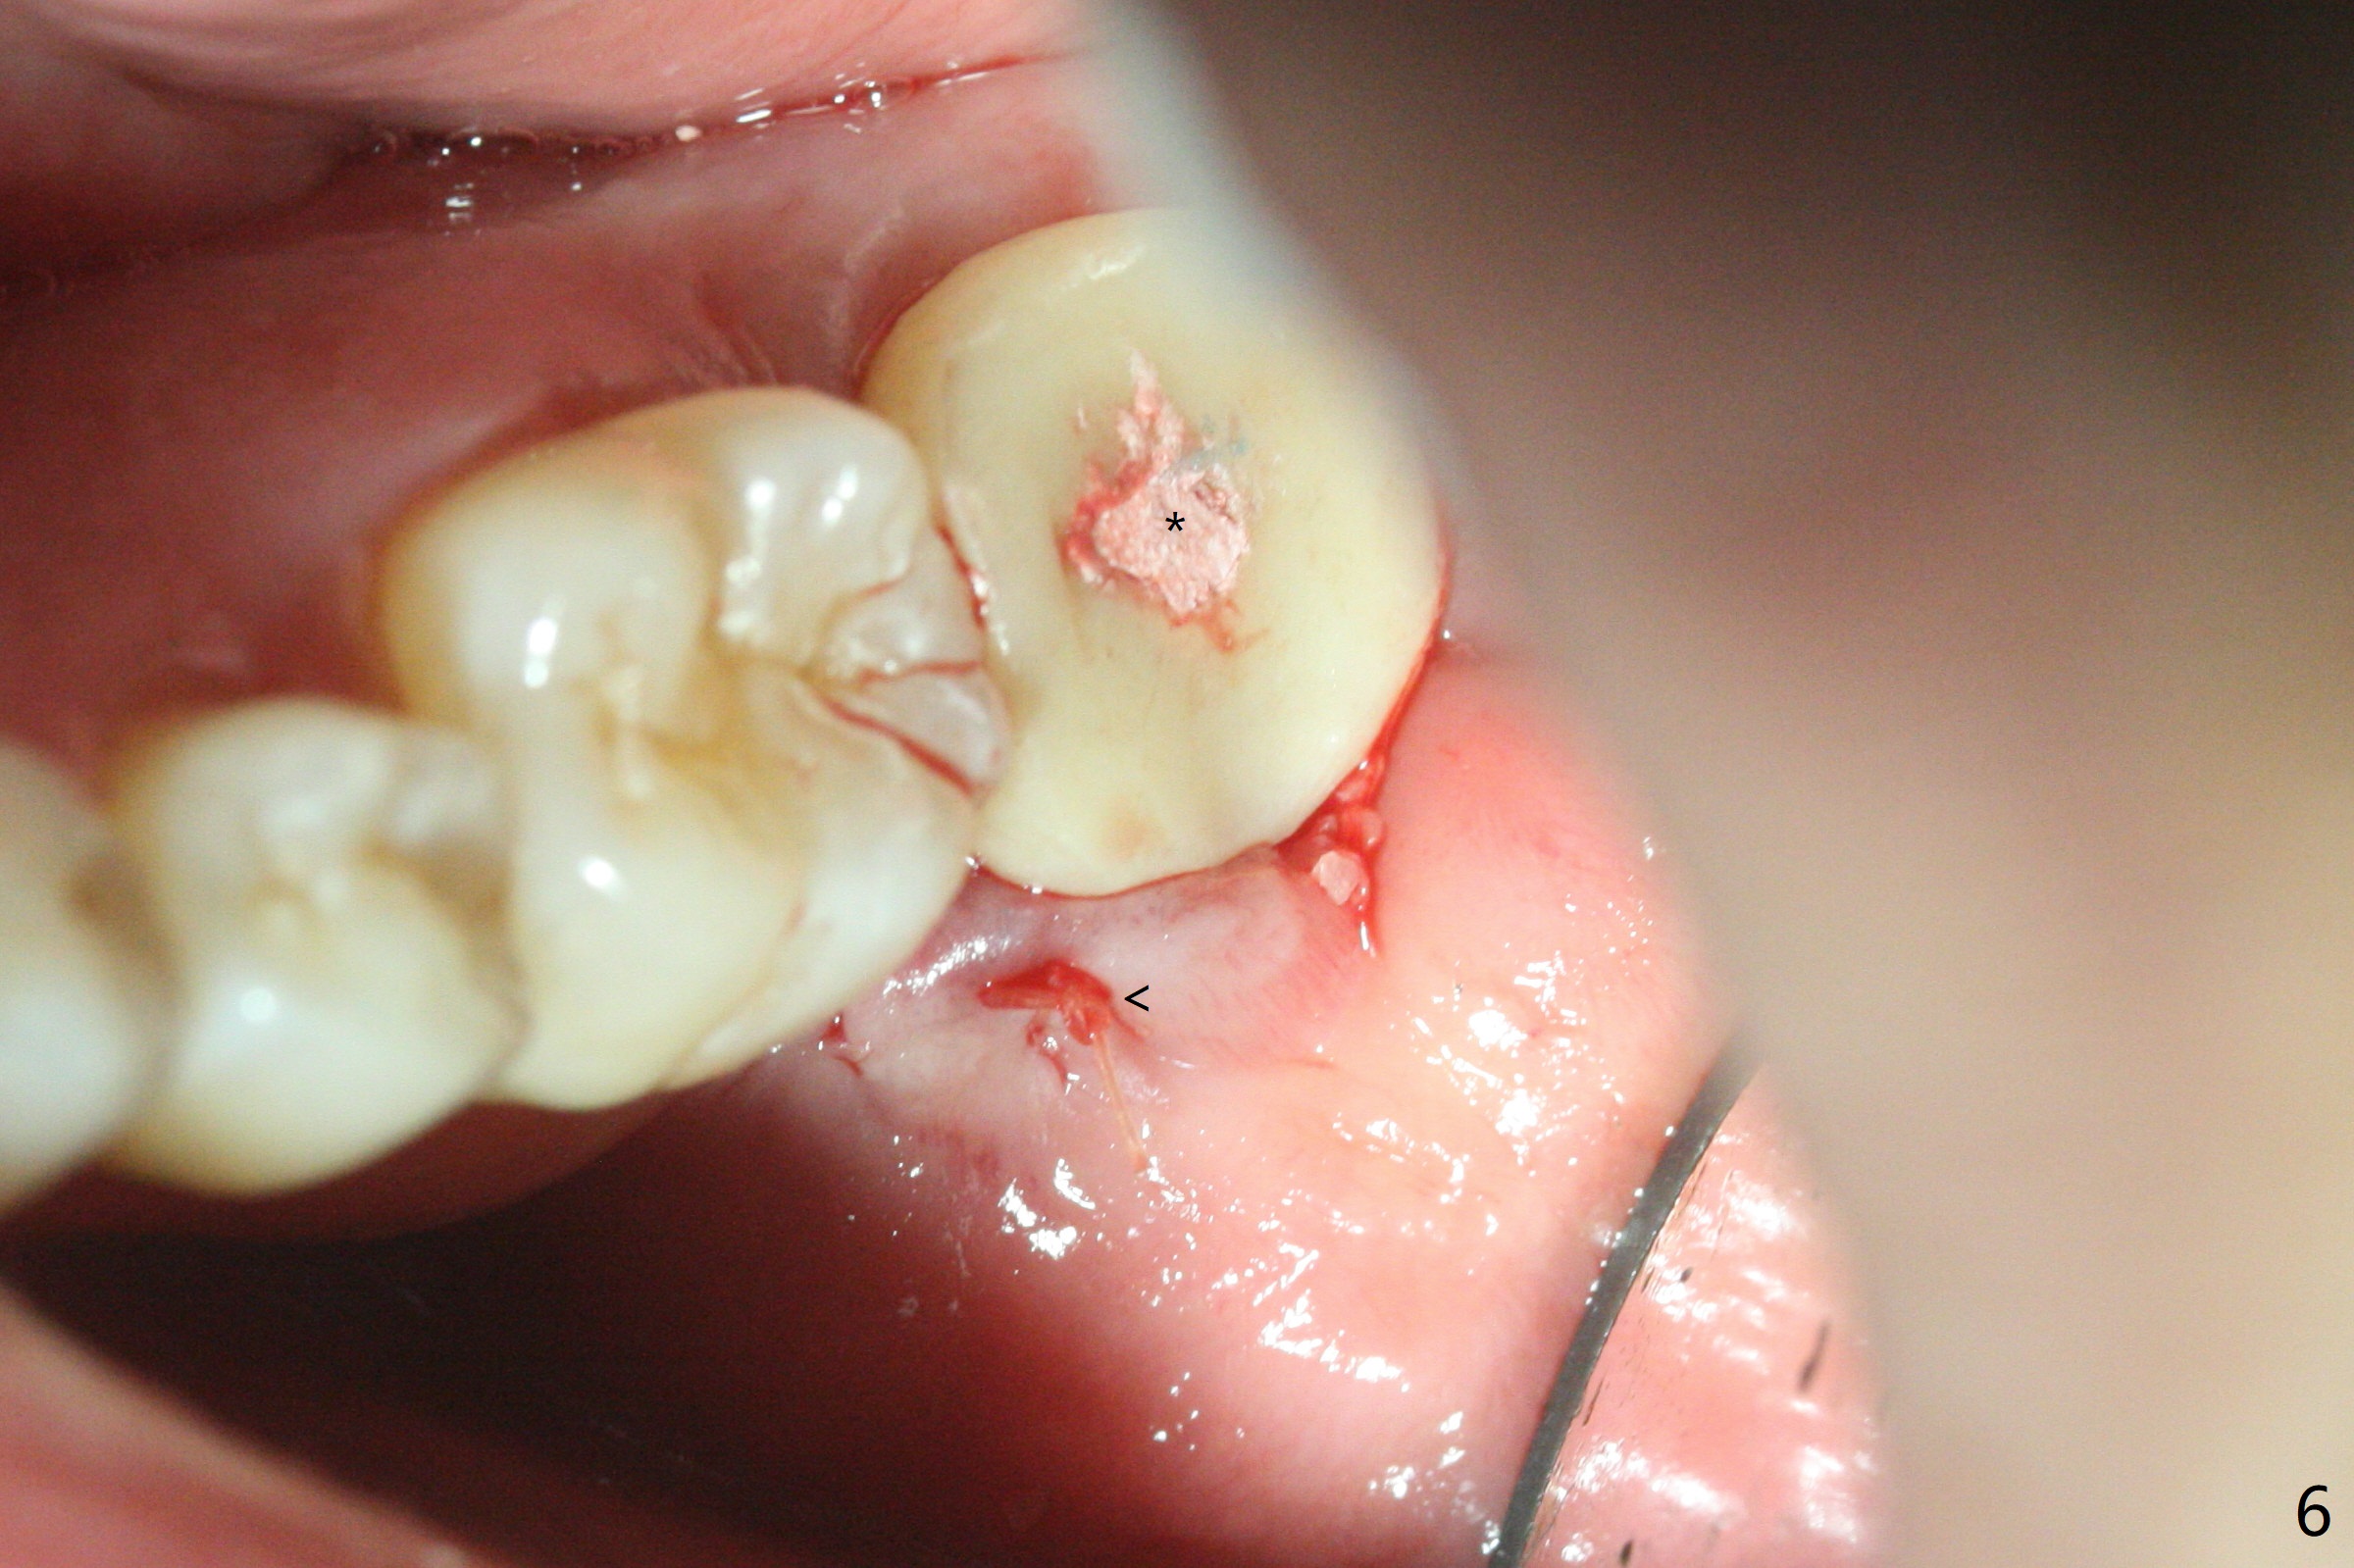

即刻种植即刻修复偶尔出现骨粉丧失,今天我们尝试临时基台,它可以制作像螺丝固位牙冠,可能会减少骨粉流失。左下7颊侧肿胀(图一:*),为了让植体(图二:绿色)植入中隔正中,钻洞时保留近中(M),远中(D)牙根。但是意想不到的是在导板指引下,钻头还是偏移近中(图三),而且颊侧(图四:圆圈),不过颊侧骨板没有缺损。由于牙根存在(硬),钻洞吃力,之后拔除,完成最后一个钻头,放置植体(图五),方位仿佛不错,临时基台(5.2x8(2)毫米)也完全就位,树脂围绕基台制作临时牙冠(图六),最后使用螺丝固位(*),颊侧肿胀牙龈必须用缝线固定(<),减少骨粉损失。由于牙冠与基台连接不好,病人汇报有些骨粉丢失。术后一个月检查尚可愈合正常,病人满意,已经做好思想准备做右下第二磨牙种植。临时牙冠进行修整。术后即刻近中牙槽窝间隙由粘性骨粉充填(图五),四个月后间隙消失(硬骨板也消失,图七),5.2x5(3)毫米粘固基台似乎没有完全就位,可能因为远中牙槽嵴阻挡(图七:*)。小一号基台仿佛完全就位(图八(咬翼片);图七(根尖片,可能失真)),但是临床上没有听到清脆声音(可能软硬组织阻挡)。随着时间推移,远中牙槽嵴吸收,当松动基台螺丝再次拧紧,可能会真正完全就位,必须拍摄完美咬翼片证实。这种植体芯(body, not threads)特别厚内部结构看不清楚。两周后粘固牙冠,然后取出牙冠和基台,清除残余粘固剂,然后复位,拧紧30Ncm。